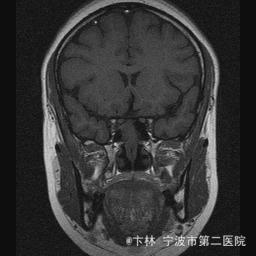

40岁女性,因“双眼视力下降三月余伴停经1个月余”入院。 患者三月前无明显诱因下出现双眼视力下降,视物模糊,尤以左眼为甚,只能近距离看到手动,无头痛、头晕,无恶心、呕吐,无视物旋转,无行走困难等不适,患者曾在某眼科医院就诊治疗,考虑为双眼视神经炎,予以营养,补液对症等治疗(具体不详),情况不见好转,近一月来患者月经停止,来我院神经外科门诊,予以查头颅CT,头颅MRI,提示“垂体大腺瘤”,为求进一步治疗收住入院

予以完善血,尿,粪常规检查,及凝血功能全套,输血功能全套及垂体功能全套,蝶鞍冠状CT等术前检查措施,行经蝶入路垂体瘤切除术。术后予以对症,补液,调节血电解质等治疗,患者视力明显改善,复查头颅MRI提示肿瘤基本全切,一周后患者出院。

此病人颅内垂体瘤体积较大,突破鞍隔压迫视交叉,故患者视力视野障碍为首发症状,该肿瘤主体有大部分向蝶窦腔生长,因此采用经蝶手术入路,肿瘤切除满意,术后患者视力视野恢复满意,。